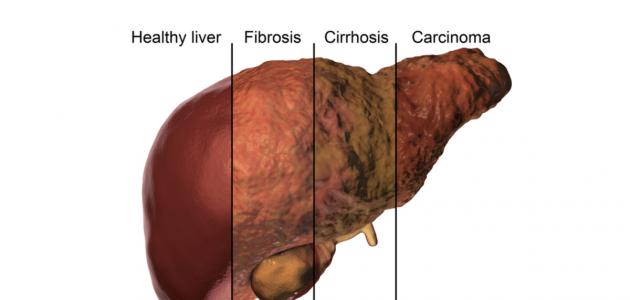

إنّ تليف الكبد (بالإنجليزية: Liver fibrosis) وتشمّع الكبد (بالإنجليزية: Liver cirrhosis) من الأمراض التي تُصيب الكبد وتؤثر في قدرته على أداء وظائفه، إذ يحدث تليف الكبد نتيجة تشكّل نسيج ندبي في الكبد استجابةً للإصابة بأمراض الكبد المزمنة؛ مثل: الإصابة بالتهاب الكبد الوبائي “ب” أو”ج”، أو مرض الكبد الدهني غير الكحولي (بالإنجليزية: Fatty liver disease) سواء الكحولي أم غير الكحولي، وهذا بحدّ ذاته يؤثر في قدرة الكبد على العمل بكفاءة، ومع مرور الوقت وتزايد الندبات، قد يؤدي ذلك إلى تطوّر حالة تشمّع الكبد،[١][٢] ولكن عادةً ما يستغرق الأمر سنوات حتى تصل الحالة إلى هذه المرحلة كما ويمكن أن يُساعد العلاج في إبطاء تطورها، وتجدر الإشارة إلى أنّ تليف وتشمّع الكبد ليسا مرضيين بحدّ ذاتهما بل هما ناتجين عن عواملٍ أدت إلى تلف الكبد،[٣][٤] وبمجرد تطور الحالة للتشمّع فإنّ ذلك يزيد من احتمالية حدوث بعض المضاعفات الخطيرة، مثل: ارتفاع ضغط الدم البابي (بالإنجليزية: Portal Hypertension)، أو فشل الكبد (بالإنجليزية: Liver failure)، أو سرطان الكبد (بالإنجليزية: Liver cancer).[٣]

يحدث تليّف الكبد نتيجة تعرض الكبد بصورةٍ مستمرةٍ أو متكررةٍ للضرر والتلف الذي يؤثر فيه، فكلمة تليّف تُشير إلى تندُّب الكبد بسبب تعرضه لعمليات التئام غير منتظمة ومتكررة، ومن الجدير ذكره أنّ الكبد يقوم عادةً بإصلاح نفسه وتكوين خلايا كبديّة جديدة بصورةٍ طبيعية، وعليه فإنّ تكرار الإصابة أو استمرارها لمدةٍ طويلة سيكون مصحوبًا بمحاولة خلايا الكبد إصلاح الأضرار باستمرار، وهذه المحاولات قد تتسبّب بتكوين نسيج ندبيّ يحلّ محل خلايا الكبد الطبيعية، ويُشار إلى أنّ هذه الندبات لا تؤدي أيّ وظيفة بل إنّها تؤثر في بُنية الكبد وقد تتداخل مع عملية التدفق الطبيعي للدم من الكبد وإليه، وذلك من شأنه أن يقلل من تدفق الدم لخلايا الكبد، وقد يترتب على ذلك موت الخلايا وتكوّن المزيد من الندبات، والتي بدورها قد تتطور لتكوين التليف، وقد يحدث التليّف بشكلٍ أسرع عندما يكون ناجمًا عن حدوث انسداد في القنوات الصفراويّة (بالإنجليزية: Bile Ducts)، وفي بعض الأحيان يمكن السيطرة على التليّف إذا تمّ تحديد الأسباب وتداركها بالطريقة الصحيحة، أمّا في حال استمر التليّف لفتراتٍ زمنيةٍ طويلةٍ واستمر التليّف وانتشر في الكبد؛ فقد يؤدي ذلك إلى تدمير البنية الداخلية للكبد وتأثّر قدرته التجدّد والقيام بوظائفه الأخرى، ويُعرف التليّف الشديد في هذه الحالة بمصطلح تشمّع الكبد؛ وعليه فإنّ تشمّع الكبد ما هو إلّا مرحلة متقدمة جداً من التليّف.[٥][٤]